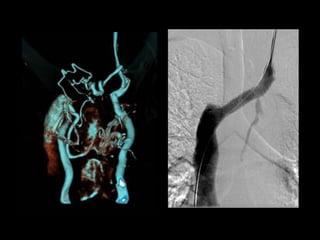

65M with metastatic lung ca and recent PEs. An IVC filter was placed but did

not fully deploy. A second IVC filter was placed above the first one.

120cc contrast, diagnostic delay = 70sec